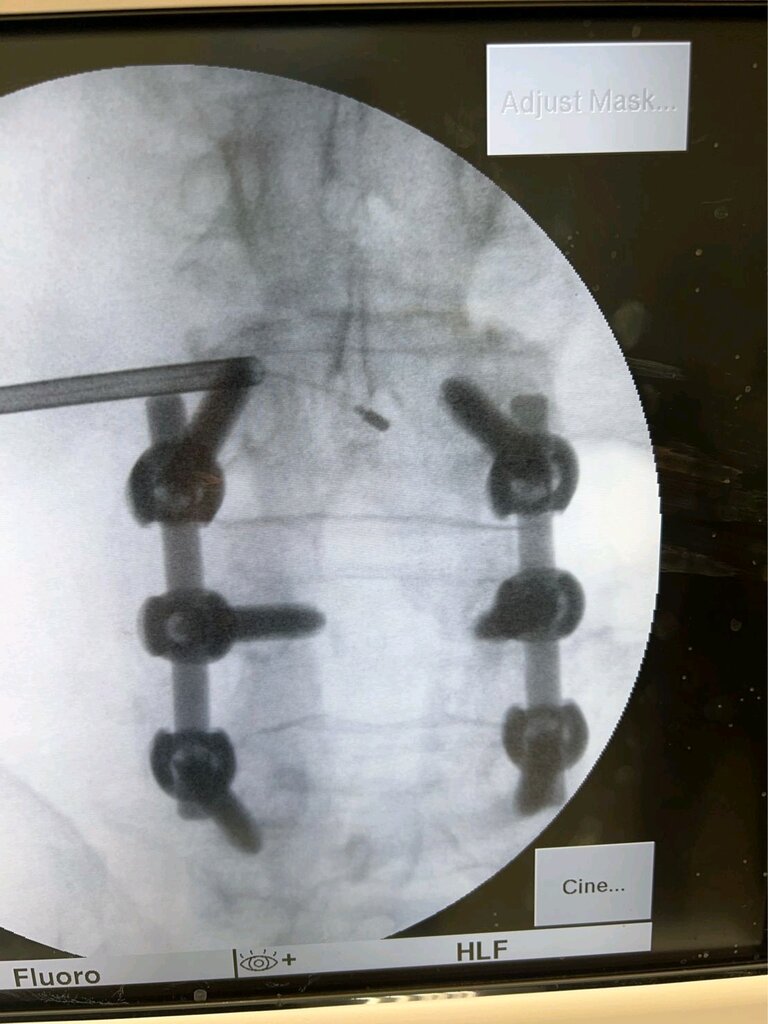

Doug Beall going over the top of screw

image_d763a6f2-305e-4d46-948b-68926a28257620220714_162000.jpg

image_b1888c74-3b51-4a67-af3a-4fc0d9216f5a20220714_161956.jpg

image_5c396b3d-57d1-4a7d-8f47-79217506a40e20220714_161954.jpg

image_c8082d3b-519b-4414-a67e-0560bf23415e20220714_161949.jpg